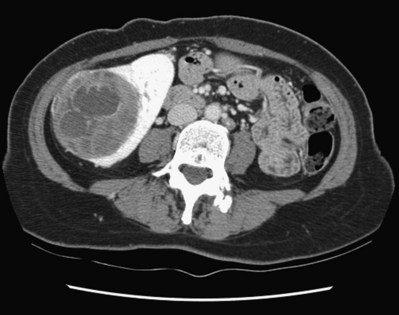

Because of the higher risk of malignancy associated with Bosniak class III and IV lesions, therapy is recommended (Fig. 51–2). The definitive therapy would be surgical excision, although ablative therapies such as cryotherapy or radiofrequency ablation of cystic masses have been reported (Raman et al, 2009) (see Chapter 49).

Figure 51–2 A, CT scan of a Bosniak III renal cyst. Thick, irregular septations are present within the cyst. B, CT scan of a Bosniak IV renal cyst, with a solid enhancing nodule. C, Bivalved Bosniak IV renal cyst demonstrating a solid component that proved to be conventional renal cell carcinoma.